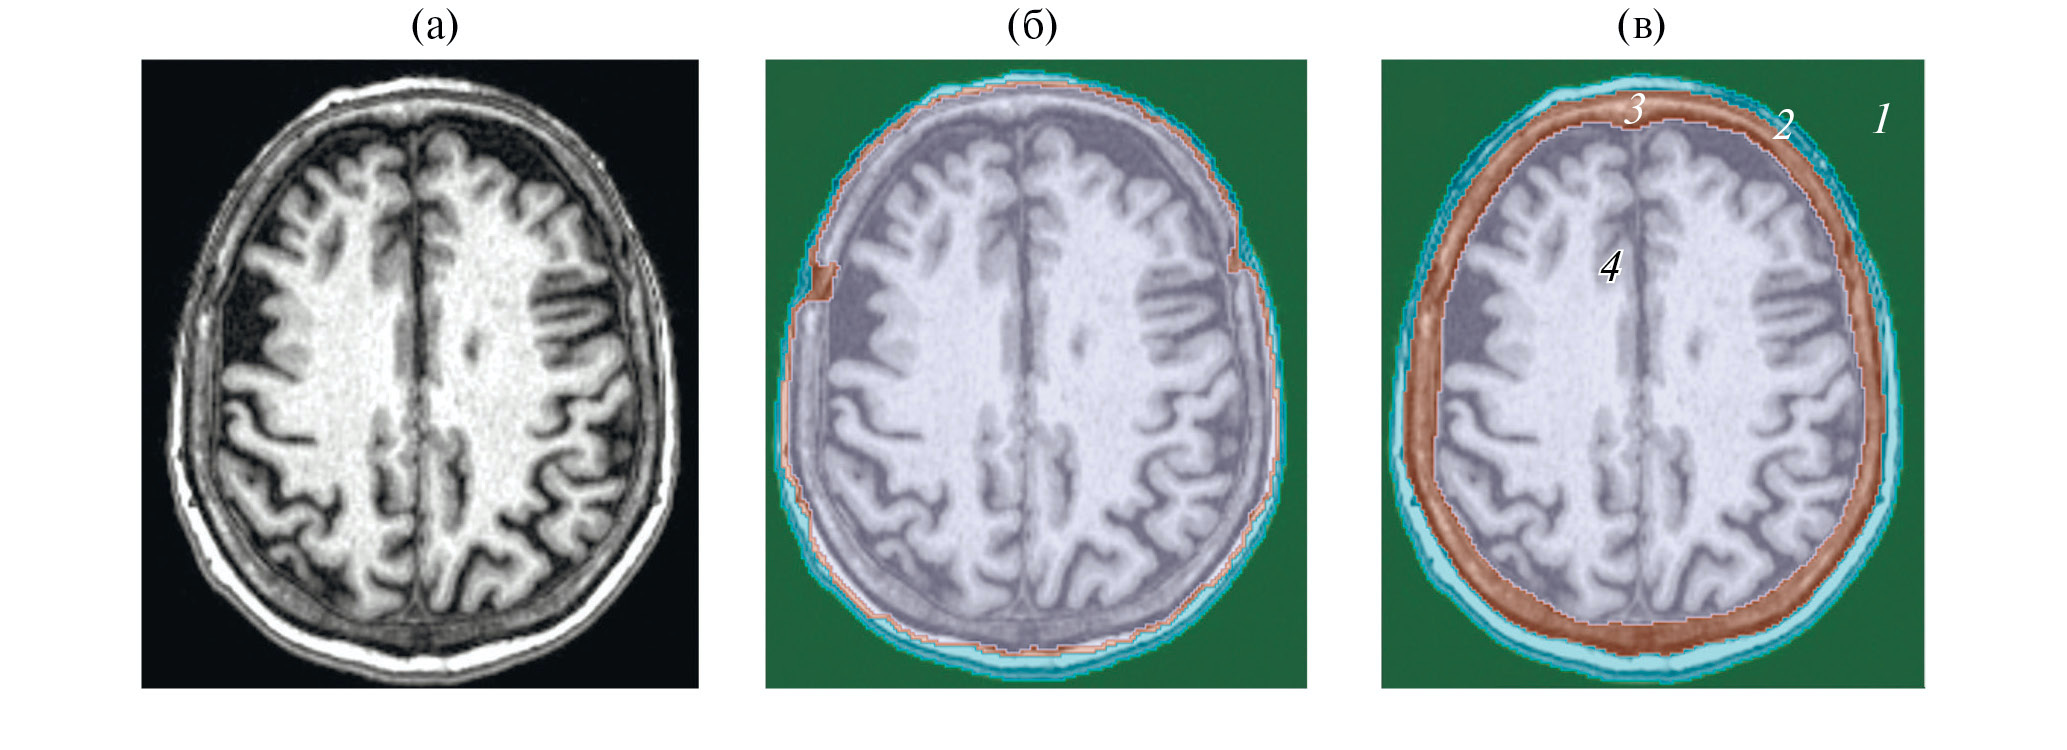

Чтобы задать коэффициент поглощения, необходимо сегментировать КТ-изображения и выделить основные сегменты – кожу, череп и мозг, коэффициент поглощения для которых известен из справочной литературы [19]. Сегментация КТ-изображений в данной работе была проведена с помощью открытого программного обеспечения Slicer (slicer.org) [20]. Благодаря сильно различающимся значениям пикселей по шкале Хаунсфилда в кости и мягких тканях, к КТ-изображению возможно было применить метод пороговой сегментации. С помощью этого метода и дополнительных функций программы Slicer (flood filling, islands, logic operations) в отдельные сегменты были выделены мозг, череп, кожа и согласующая среда (вода) (рис. 1).

Рис. 1. Аксиальный срез компьютерной томографии головы человека (а) – до проведения сегментации, (б) – до проведения сегментации с другим контрастом, (в) – после сегментации в программе Slicer. Сегменты отмечены цифрами: 1 – внешняя среда (вода), 2 – кожа, 3 – череп, 4 – мозг.